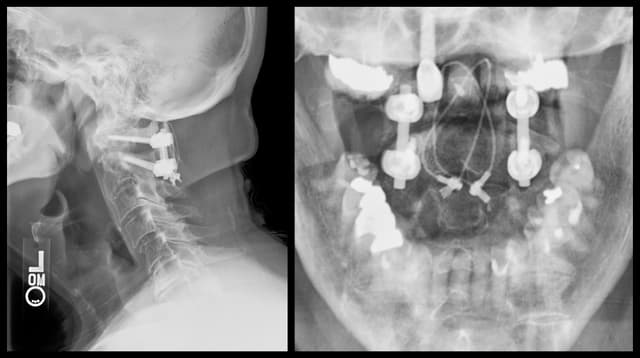

C1-2 Fusion

Post-op